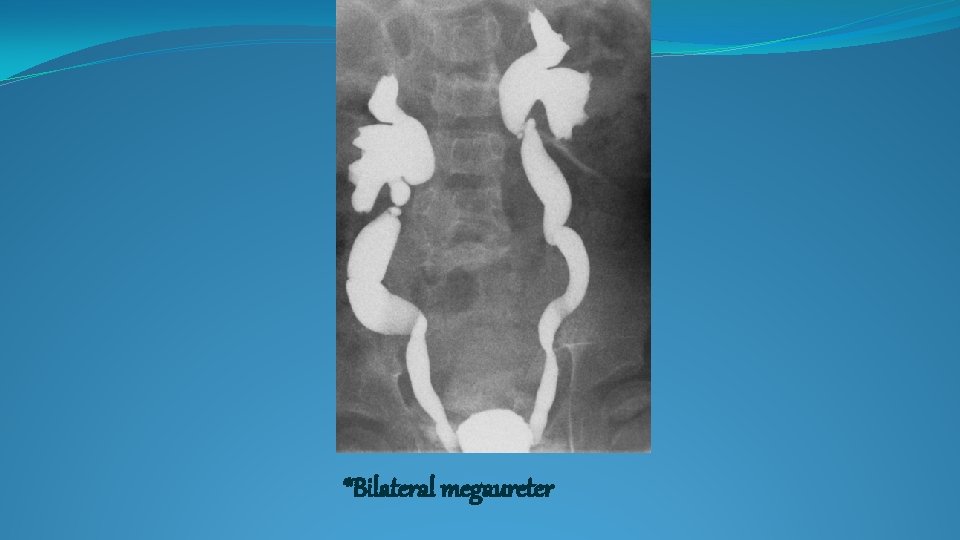

*Bilateral megaureter